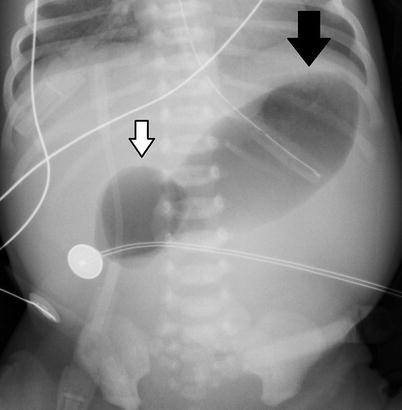

Medical News Radiology Mcqs For Usmle Aipgee And Plab Double Bubble Sign Causes Include A Congenital Obstruction Duodenal Web Duodenal Atresia Duodenal Stenosis Annular Pancreas B

シングルバブル、ダブルバブル、トリプルバブルサインの違い なになにバブルサインとは、消化管が閉鎖される疾患のレントゲン所見のこと。 シングルバブルサイン ダブルバブルサイン トリプルバブルサイン 画像 出典 出典:105D41 出典スクリーン ダブルバブル クリア honda vtr1000f '97 〜 '05 カラー:クリア タイプ:ダブルバブル ご注意 写真は実際の製品と異なる場合がございます。 16年3月22日からの新価格です。Double(ダブル)は、日本の女性 歌手、ソングライター、takakoによるソロ・プロジェクト。 姉妹デュオとして1998年にデビューしたが、1999年に姉のsachikoが急逝したため、以降は現在の形態となった。 06年からはdj lilly aka double(ディージェイ・リリー・エーケーエー・ダブル)名義

bubble バブル の値段はいくら? 今回はTWICEの画面で紹介するけど bubble バブル のアプリから値段を確認できるよ。 ここで注意したいのが、bubbleの登録はNiziUメンバー1人の値段ね。でも複数メンバー登録すると割引もあるよ。ダブルバブルサイン 上部消化管閉塞 十二指腸閉塞 ダブルマドックス杆検査 上部消化管閉塞 先天性消化管異常 メルクマニュアル18版 日本語版 特徴的徴候は,唾液過多,哺乳を試みた後の咳嗽とチアノーゼ,嚥下性肺炎である。 食道 遠 ★リンク